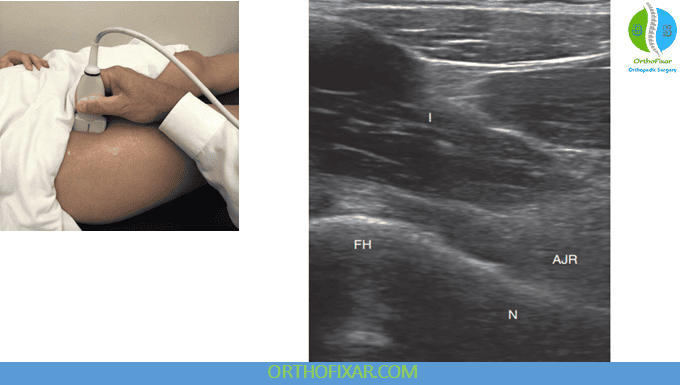

The anterior portion of the adult hip ultrasound examination is typically performed with the patient in a supine position.

- Place the transducer in a longitudinal plane, aligned with the femoral neck.

- This oblique orientation follows the natural axis of the femoral neck.

- Contour of the femoral head, femoral neck, and acetabulum

- Anterior joint recess, where joint effusion or synovitis may appear as swelling or excess fluid

- Labrum, which should appear hyperechoic and triangular proximally